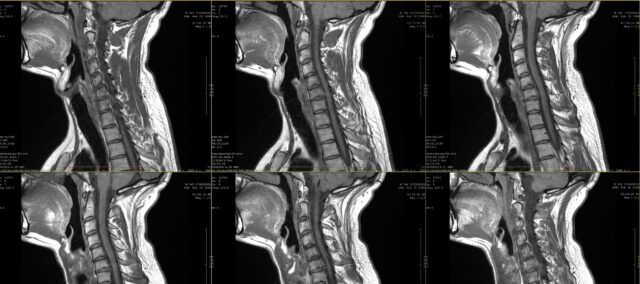

Servikal radikülopati seviyesinin belirlenmesi

Radiküler ağrı çizimleri ile MRG bulguları arasındaki uyumu araştırmak amacıyla, bu çalışmaya 2 aylık inatçı ağrı öyküsü olan ve MRG'de servikal radikülopati tanısı konulan katılımcılar dahil edilmiştir. Bu tanı bir beyin cerrahı tarafından klinik bilgilere ve bir radyolog tarafından değerlendirilen MRG bulgularına dayanılarak konulmuştur.